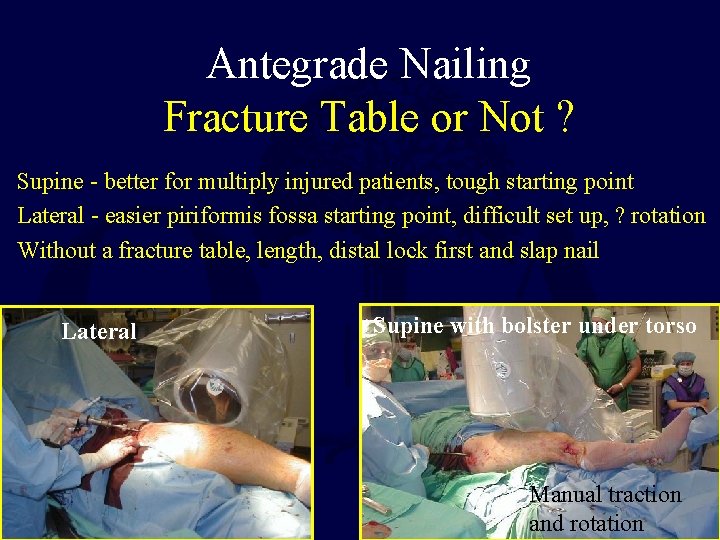

Antegrade Nailing Fracture Table or Not ? Supine - better for multiply injured patients, tough starting point Lateral - easier piriformis fossa starting point, difficult set up, ? rotation Without a fracture table, length, distal lock first and slap nail Lateral Supine with bolster under torso Manual traction and rotation